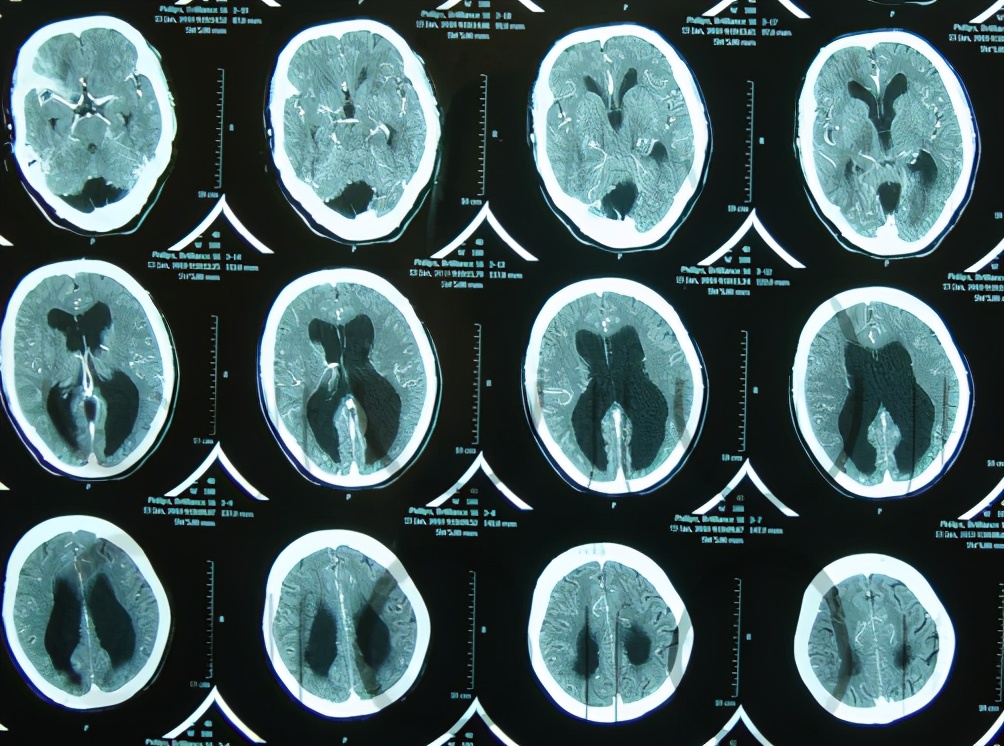

7岁儿童脑出血后脑积水,腰大池引流术后加重感染

典型的左中后颅窝占位